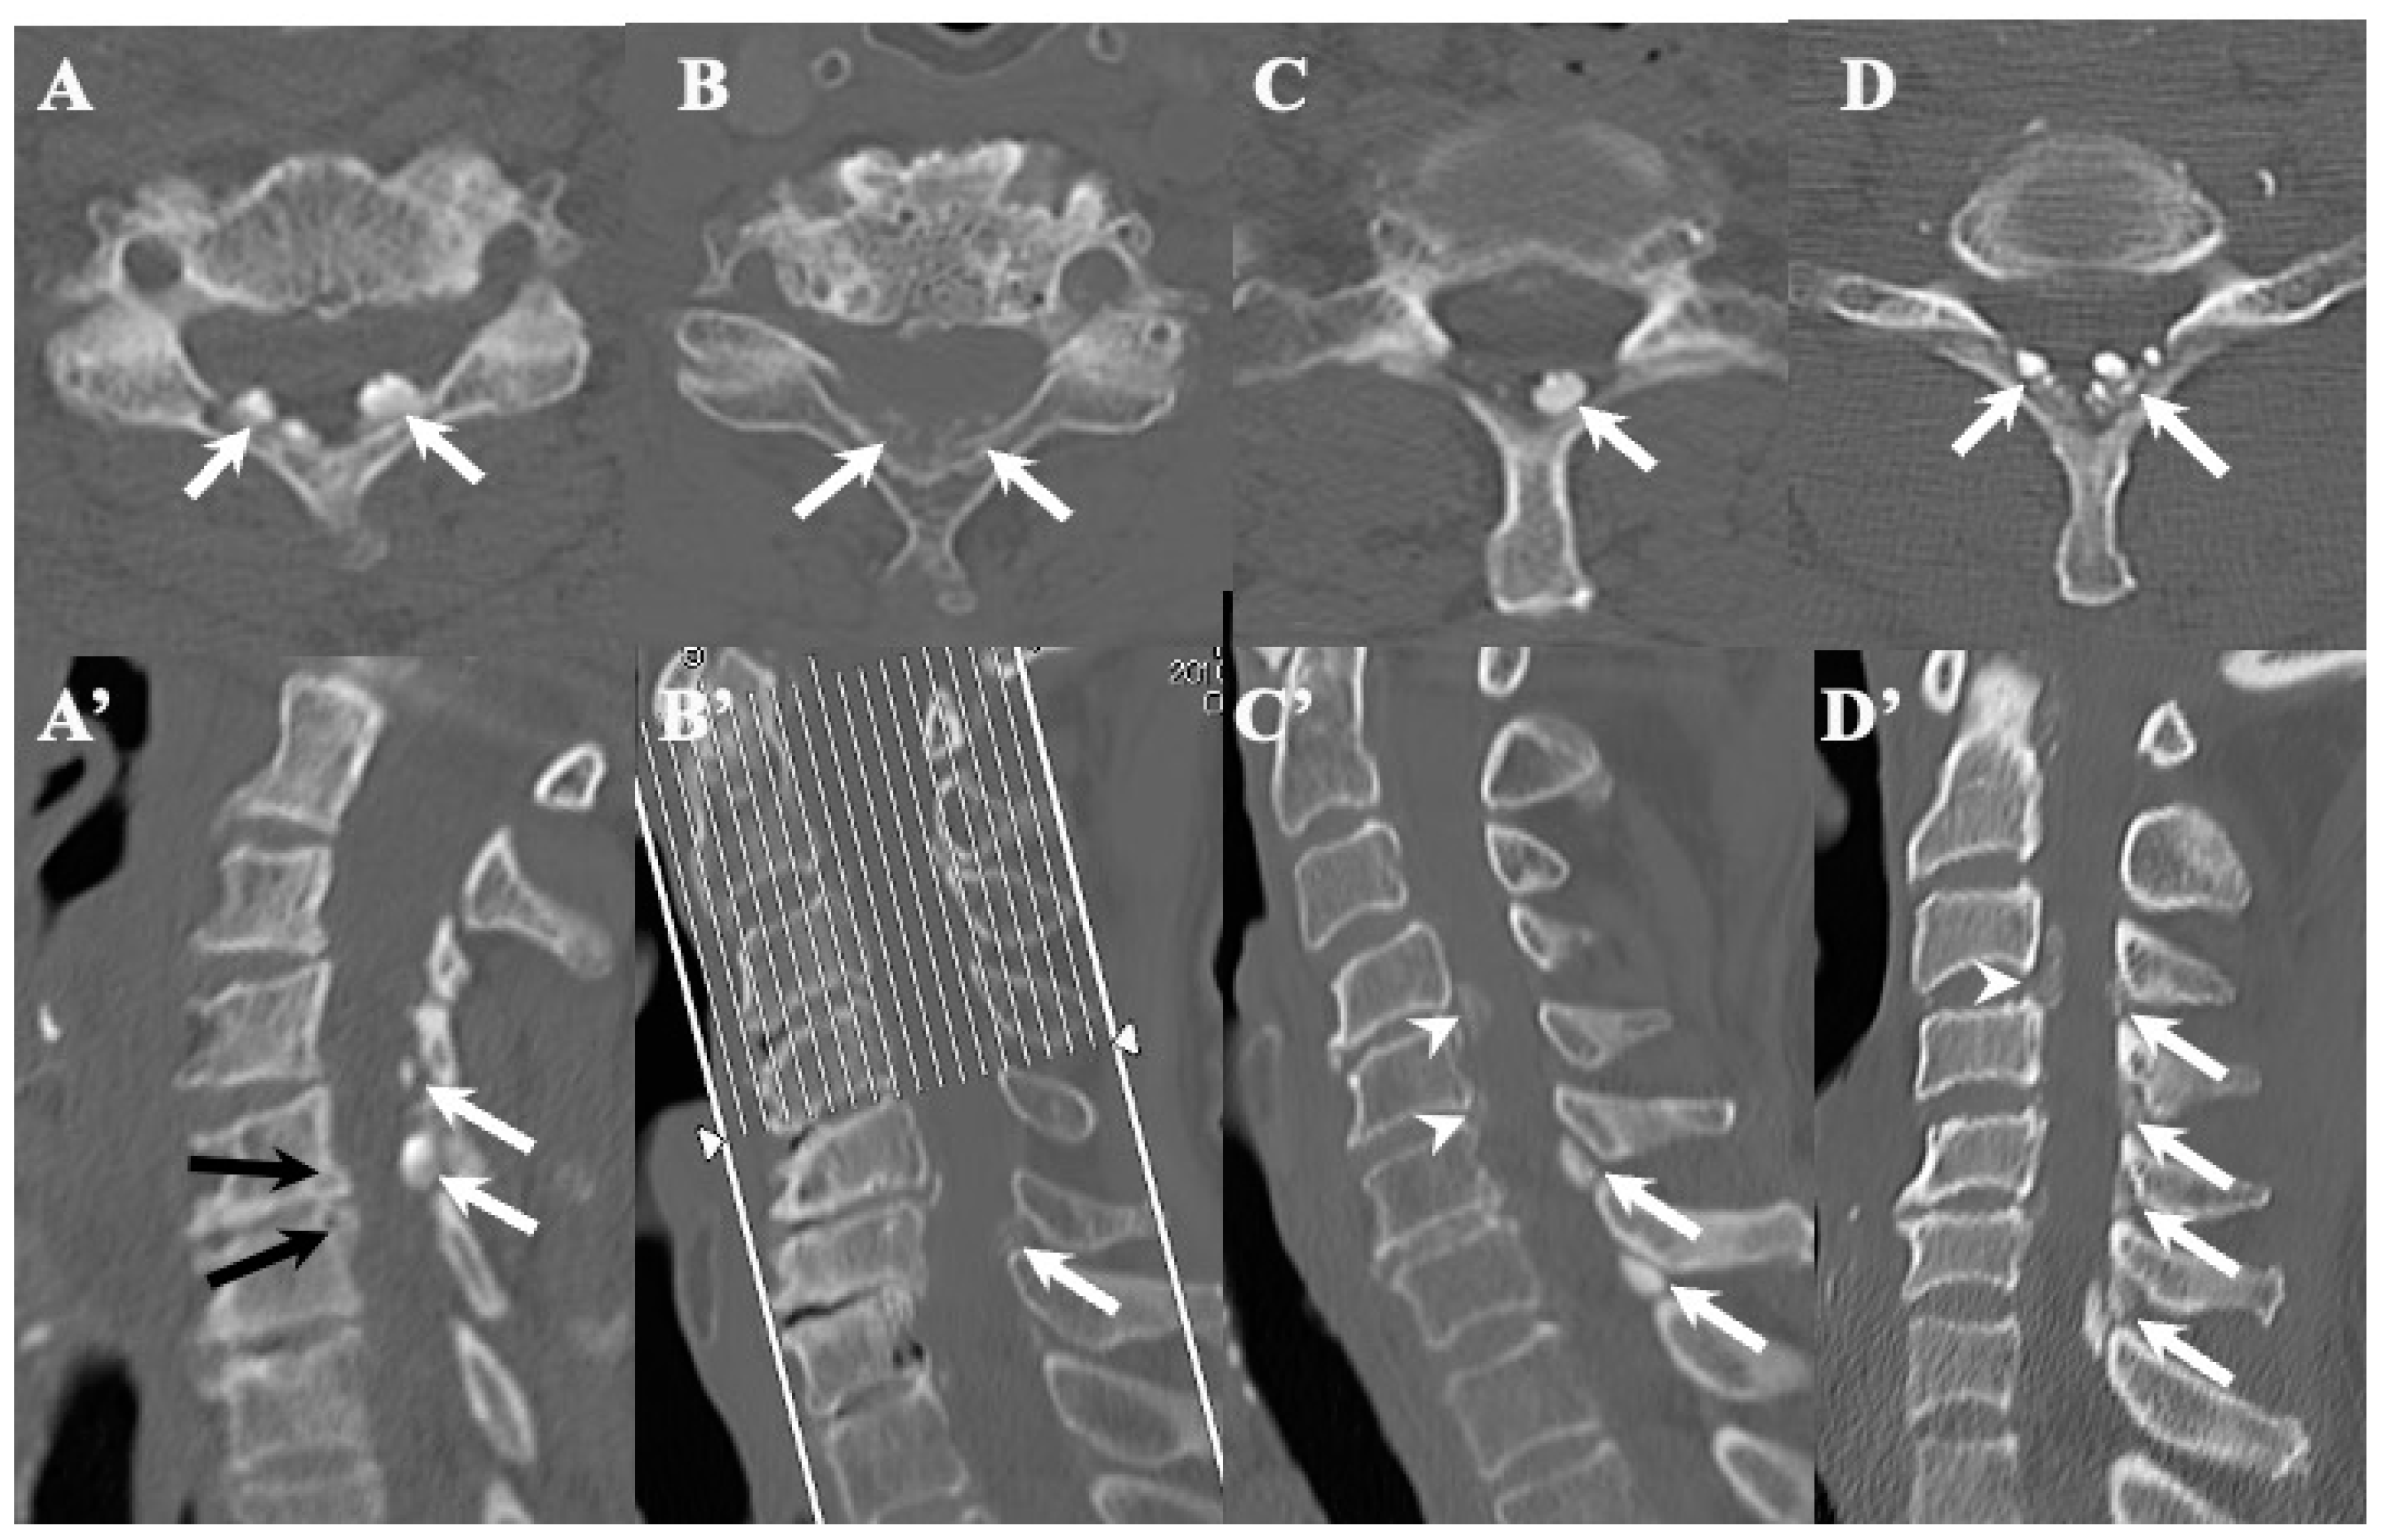

3.3. Neuroradiological Findings (Figure 3, Figure 4, Figure 5 and Figure 6; Table 3)

CLF: All cases exhibited spondylotic changes. Developmental narrowing (anterior-posterior diameter of spinal canal < 12 mm) of the spinal canal was observed in five cases, disc herniation in four cases, and ossification of the longitudinal ligament in three cases. Two-dimensional (2D)-reconstructed CT images demonstrated “multiple islands of speck-like and egg-shaped” high-density mass, “diffuse and speck-like” high-density masses, and/or “egg-shaped” high-density masses in the ligamentum flavum (Figure 3). In three cases, there was ossification of the longitudinal ligament (Table 3). MR T2-weighted images showed these mass lesions as areas of low intensity or isointensity, with compression of the spinal cord. The presence of both low-intensity and isointense regions suggested a combination of calcification and ligamentum tissue (Figure 4). In five cases, dynamic X-rays of the cervical spine demonstrated instability of joints (Table 3).

Figure 3.

Two-dimensional CT images of CLF. Two-dimensionally reconstructed CT scan axial image (A) and sagittal image (A’) CT scan demonstrating “egg shape” high-density mass contacting with laminae (arrows) and posterior osteo-spur at the C5/6 intervertebral level (black arrows). Two-dimensionally reconstructed CT scan axial image (B) and sagittal image (B’) demonstrating “diffuse and speck like” high-density mass contacting with laminae in ligamentum flavum (white arrows). Two-dimensionally reconstructed CT scan axial image (C) and sagittal image (C’) demonstrating “egg shape” high-density mass in ligamentum flavum on the left side in (C) and along the ligamentum flavum in (C’) (white arrows), ossification of posterior longitudinal ligament at the C4/5, 5/6 (white arrowheads), and listhesis at C3/4 intervertebral level. Two-dimensionally reconstructed CT scan axial image (D) and sagittal image (D’) demonstrating “multiple islands of speck like and egg shape” high-density mass in ligamentum flavum (arrows) and ossification of longitudinal ligament at C3/4 (white arrowhead).

OLF: There were spondylotic changes in 17 cases, developmental narrowing of the spinal canal in 7 cases, disc herniation in 7 cases, ossification of the longitudinal ligament in 4 cases, diffuse idiopathic skeletal hyperostosis (DISH) in 4 cases, and ankylotic spinal hyperostosis (ASH) in 3 cases [31,51,52]. Two-dimensionally reconstructed CT images showed beak-like ossification extending into the intervertebral foramen (Figure 5) (Table 3). MR T1-weighted and T2-weighted images demonstrated low-intensity masses in the dorsal spinal canal, which compressed the spinal cord. In some cases, there were high-intensity spots, suggesting the formation of bone marrow (Figure 6). In three cases, dynamic X-rays of thoraco-lumbar spine demonstrated joint instability (Table 3).

Figure 5.

Two-dimensional CT images of OLF. Two-dimensionally reconstructed CT scan sagittal images (A–D) image and axial image (A’–D’) showing beak-like ossification extended to intervertebral foramen (white arrows).

4.2. Comparison of Neuroradiological Findings between CLF and OLF (Figure 3, Figure 4, Figure 5 and Figure 6; Table 3)

CLF: A two-dimensionally reconstructed CT scan revealed “multiple islands of speck-like and egg-shaped” high-density mass and/or “diffuse and speck-like” high-density mass within the ligamentum flavum. MR T1- and T2-weighted images depicted these mass lesions as low intensity or isointense, with compression of the spinal cord. The presence of low-intensity and isointense regions suggested a combination of calcified regions and ligamentum tissue (Table 3, Figure 1 and Figure 2) [3,4,6,7,9,10,12,14,15,17].

OLF: Two-dimensionally reconstructed CT scan images showed beak-like ossification extending into the intervertebral foramen. MR T1-weighted and T2-weighted images demonstrated a low-intensity mass within the dorsal spinal canal compressing the spinal cord. In some cases, the presence of high-intensity spots suggested bone marrow formation (Figure 3 and Figure 4) [18,26,29,30,31]. In some cases, OLF was associated with DISH and ASH, indicating a more generalized ossification pattern (Table 3). Previous reports have reported the association of DISH and ASH in OLF, but the specific features of this association were unclear [51,52]. In both CLF and OLF, spondylotic changes were the most common associated condition, followed by disc herniation and instability. This suggested that chronic micro-movement and mechanical stress (traction, rotation, and compression) to the ligament were contributing factors (Table 3).